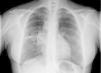

Pancreatitis aguda como síntoma inicial de un tumor de célula pequeña pulmonar

Acute pancreatitis as an initial symptom of a small-cell carcinoma of the lung